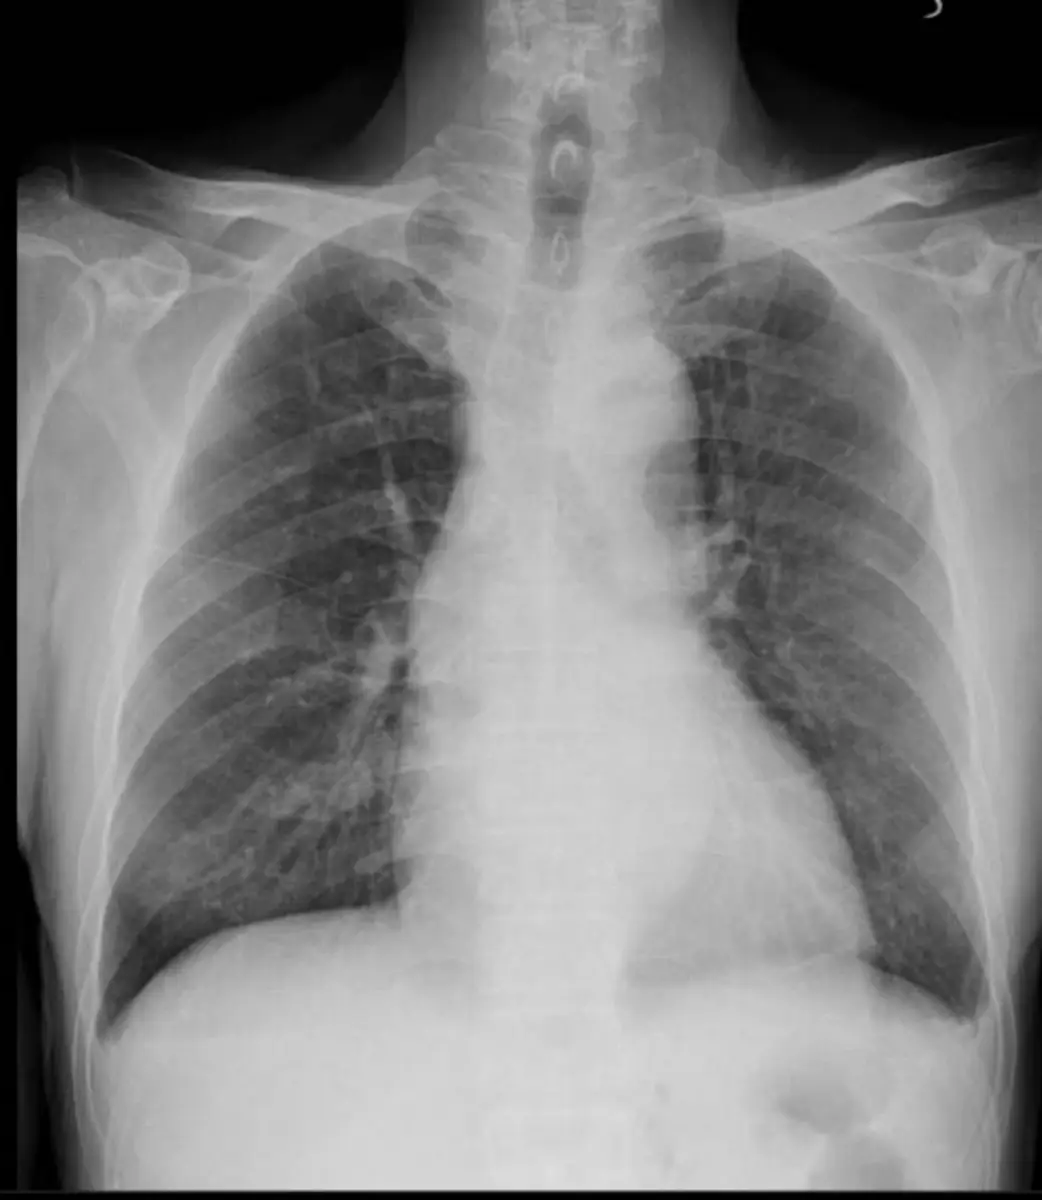

一位70歲女性病患胸痛1小時到急診,過去病史有高血壓與高血糖;但血壓控制不良,至急診時血壓為160/100毫米汞柱,糖化血色素最近數值為8.0%,最近無出血傾向或上消化出血紀錄,血氧飽和濃度(SpO2) 為98%.聽診心臟無S3奔馬音,肺部聽診無濕囉音(moist rales)或喘鳴音(wheezing),四肢皮膚溫暖且下肢無水腫,心電圖與胸部X光片如圖一及圖二。請問下列敘述何者為是? (1). 該病患應該立刻至心臟科一般病房住院,住院後應照會心臟科醫師 (2). 給予該病患阿斯匹靈 (aspirin) (3). 因血壓過高,給予短效鈣離子阻斷劑nifedipine 5mg 來降血壓 (4). 可給予病人舌下nitroglycerin (5).可給予病人乙型受體阻斷劑(beta-blocker) 圖片描述 圖片描述

2. 胸部X光片:心影不增大,肺野清晰、無明顯血管紋理增粗或濕囉音所對應的肺水腫徵象;無胸腔積液或其他肺部病灶,支持此時尚無心衰或肺水腫。